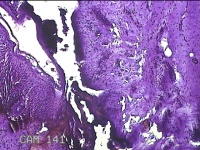

右拇指肿块

性别

女

年龄

73岁

临床诊断

右拇指肿物性质待查

一般病史

标本名称

大体所见

灰白粉红色肿物2.2x1.3x0.3cm一个,表面糜烂,切面灰白粉红色,质软。

图1